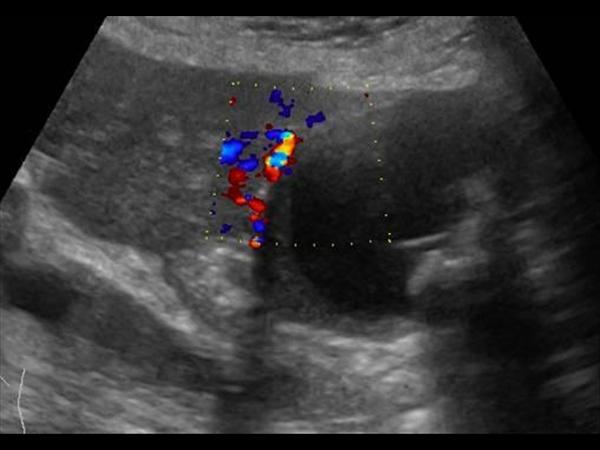

Viêm túi mật

» Thông tin: Nữ giới – 87 tuổi.

» Lâm sàng: Đau mạn sườn phải / Sốt.